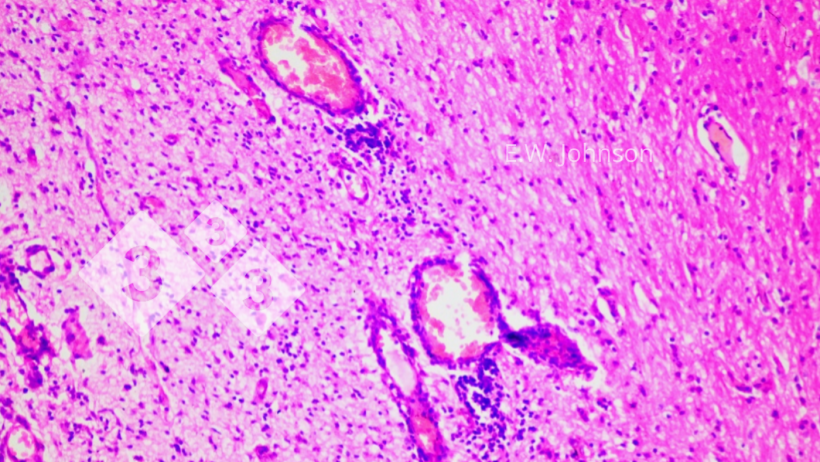

Ryc. 2. Nacieki okołonaczyniowe i glejoza. Mózg.

Badanie mikroskopowe mózgu ujawniło zapalenie opon mózgowo-rdzeniowych z naciekiem okołonaczyniowym i glejozą (ryc. 2) oraz naciek opon mózgowo-rdzeniowych z mieszanymi jednojądrowymi i wielojądrowymi komórkami zapalnymi (ryc. 3). Ryc. 3. Zapalenie opon mózgowych z komórkami jednojądrowymi i kilkoma wielojądrowymi. Mózg.